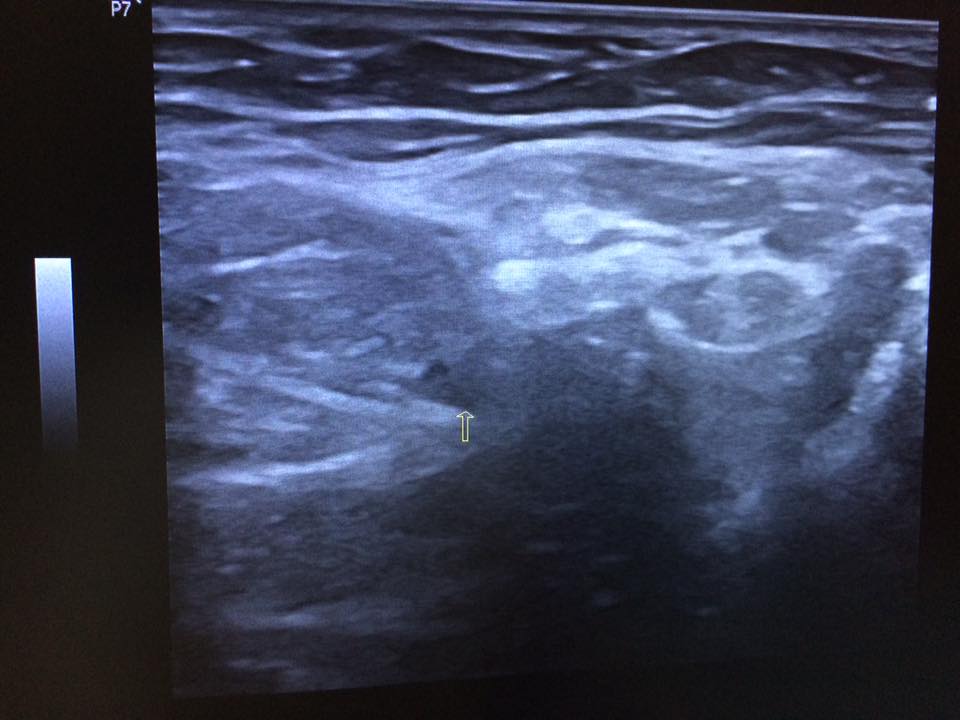

Staff member 4. Nam 67t Ls: chuẩn bị mổ thoát vị ben t => bs pt muốn sa lại trước pt Clip sa bẹn trái Chẩn đoán? 14908238_565556773642431_7094452599200745576_n.jpg 14900543_565556830309092_6731208493409609365_n.jpg 14963305_565556790309096_4643616292348455768_n.jpg 14908193_565556873642421_859291706916583555_n.jpg 14900519_565556826975759_1726480362463028455_n.jpg Nguồn: Code: https://www.facebook.com/groups/cdhaOnline/permalink/780379048767244/ Spoiler: Đáp án: Thoát vị, chưa thấy bc nghẹt... Vị trí: cổ túi thoát vị phía NGOÀI BÓ MẠCH THƯỢNG VỊ DƯỚI VÀ PHÍA TRÊN DC BẸN=> tv gián tiếp (tv giá tiếp còn 1 dh ko quan trọng là túi tv nằm dọc phía nông và ngoài so với bó mạch thừng tinh- như case này) Quan trọng và khó khăn là cắt ra dc bẹn và mm tv dưới -------------------------------------- Video này được chia sẻ với mục đích nâng cao hiểu biết và kinh nghiệm cho cộng đồng những người làm y khoa. Không vì mục đích vụ lợi nào khác. Những mô tả và kết luận bệnh lý trong video này mang tính chất tham khảo và chỉ dành cho những người có chuyên môn. Vui lòng kiểm tra thật kỹ thông tin trước khi áp dụng vào thực tế. Nếu bạn là chủ nhân video và cảm thấy không hài lòng về điều này, hãy liên hệ với chúng tôi: [email protected] You must log in or register to reply here. Share: Facebook Twitter Reddit Pinterest Tumblr WhatsApp Email Share Link